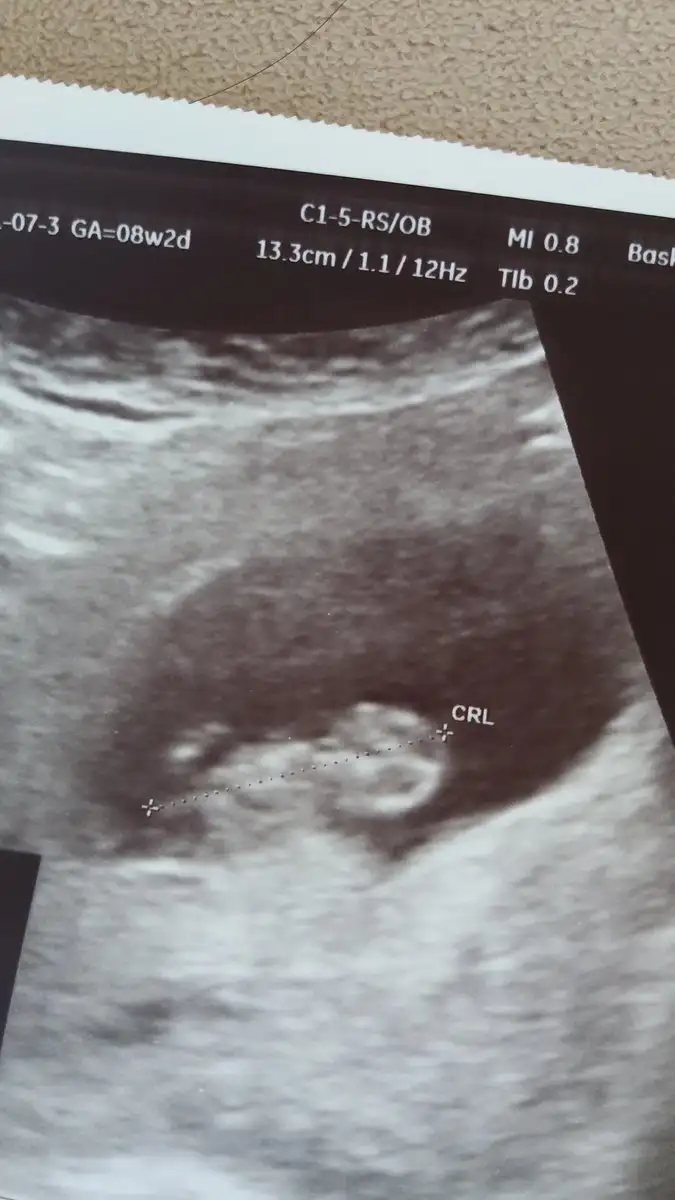

Ben 10+3 üm canım haftaya yani 11+5 iken yaptrcam ben de aldm randevu bakalım. Acaba hangi hafta yaptrmk en doğruuu??

benim doktorum 19nda gel yapalım dedi o zamana 12+3 olucam Allah nasip ederse ama şu zaman yapılır diye bir bilgim yok